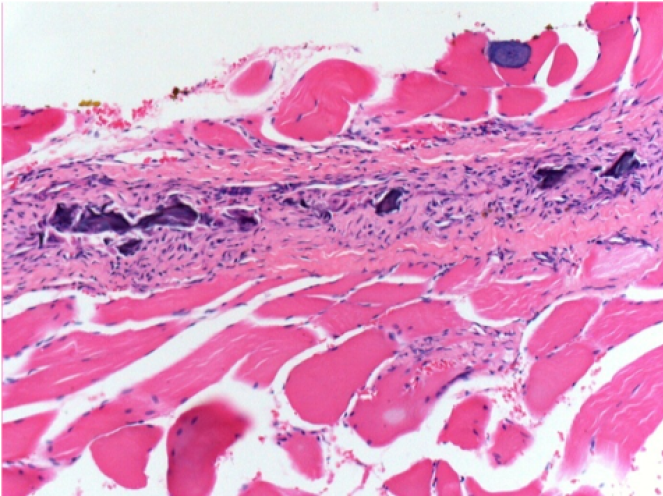

10 days after Endopeel Injection 0.1ml in the right pretibial muscle.

Here you may see the formation of the vacuoles which are surrounded by lymphocytes. Vacuoles are different from tissue necrosis . The presence of lymphocytes is related to the permeability of the cell membranes.